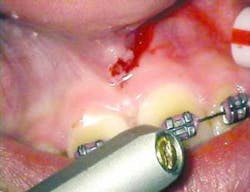

After infiltration of 1cc of local anesthetic solution, the Er:YAG laser (OpusDuo, OpusDent USA) was used at 350mj with a 1,000-micron, contact sapphire tip and heavy water spray to gently ablate the frenal attachment and underlying muscle tissue down to the level of the periosteum (figures 2, 3, and 4). Once this is accomplished, there is a small defect in the vestibular mucosa and interdental papilla where the frenal attachment and muscle once was. There is no charring, no burned tissue, and free bleeding in the site (figure 5).